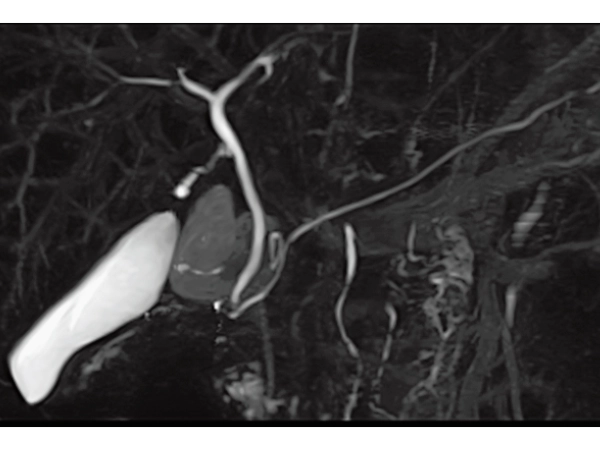

3DisoFSE MRCP (MIP)

Respiratory gating, 2:50

3DTOF MRA RADAR (MIP)

3D MRCPA (MIP)

Lower extremity

non-contrast MRA (MIP)